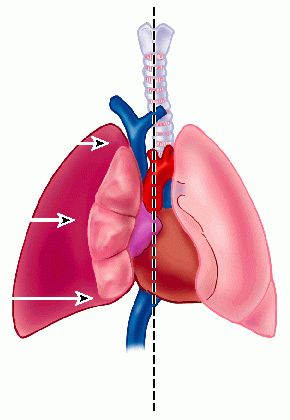

ΠνευμοθώρακαςΦυσιολογικά η πίεση στην υπεζωκοτική κοιλότητα στο τέλος της ήρεμης αναπνοής είναι μικρότερη από την ατμοσφαιρική λόγω της ισορροπίας μεταξύ της τάσεως του πνεύμονα να συμπτυχθεί και της τάσεως του πνεύμονα να εκπτυχθεί. Έτσι οι πνεύμονες μπορεί να θεωρηθούν ότι διατηρούνται σε έκπτυξη λόγω της περιβάλλουσας αρνητικής ενδοϋπεζωκοτικής πιέσεως όπως το μπαλόνι διατηρείται φουσκωμένο όταν βρίσκεται σε κενό αέρος. Όταν εισέλθει αέρας στην κοιλότητα του υπεζωκότα η ενδοϋπεζωκοτική πίεση στο πάσχον ημιθωράκιο τείνει να εξισωθεί με την ατμοσφαιρική. Όσο λιγότερο αρνητική καθίσταται η ενδοϋπεζωκοτική πίεση, τόσο αυξάνει ο βαθμός συμπτύξεως του πνεύμονα. Το μεσοθωράκιο (χώρος μεταξύ των πνευμόνων) μετακινείται προς την υγιή πλευρά λόγω της φυσιολογικής ελαστικότητας του υγιούς πνεύμονα. Αν η ενδοϋπεζωκοτική πίεση υπερβεί την ατμοσφαιρική, όπως επί βαλβιδικής επικοινωνίας της υπεζωκοτικής κοιλότητας (βαλβιδικός μηχανισμός ο οποίος επιτρέπει την είσοδο του αέρα στην υπεζωκοτική κοιλότητα αλλά όχι και την έξοδό του π.χ σε διάτρηση πνεύμονα από κάταγμα πλευράς) ή όταν ο πνευμοθώρακας αποτελεί επιπλοκή της μηχανικής αναπνοής, αναπτύσσεται πνευμοθώρακας υπό τάση. Στις περιπτώσεις αυτές ο προσκείμενος πνεύμονας συμπιέζεται, επέρχεται περαιτέρω μετατόπιση του μεσοπνευμονίου προς την υγιή πλευρά και μπορεί να παρατηρηθεί σημαντική μείωση της καρδιακής παροχής λόγω της μείωσης της φλεβικής επιστροφής προς την καρδιά, εξαιτίας της θετικής ενδοθωρακικής πιέσεως.

- Επικρουστικά υπάρχει υπερηχηρότητα (κυρίως στον υπό τάση πνευμοθώρακα) καθώς και μείωση του αναπνευστικού ψιθυρίσματος στη πάσχουσα περιοχή κατά την ακρόαση ενώ ταυτόχρονα υπάρχει και παρέκκλιση της καρδιακής ώσης προς την υγιή πλευρά.

- Η ακτινογραφία θώρακα η οποία πρέπει να γίνεται πάντα σε όρθια θέση (επειδή κατά την ύπτια κατάκλιση η προς τα άνω μετακίνηση του αέρα και η προσέγγιση των δύο πετάλων του υπεζωκότα προς τα πλάγια μπορεί να επισκιάσουν την παρουσία του) αποκαλύπτει εμφανές όριο του σπλαχνικού υπεζωκότα χωρίς σκιαγράφηση πνευμονικού ιστού μεταξύ του ορίου αυτού και του θωρακικού τοιχώματος καθώς και μετακίνηση του μεσοθωρακίου και παρέκκλιση της τραχείας προς την υγιή πλευρά.